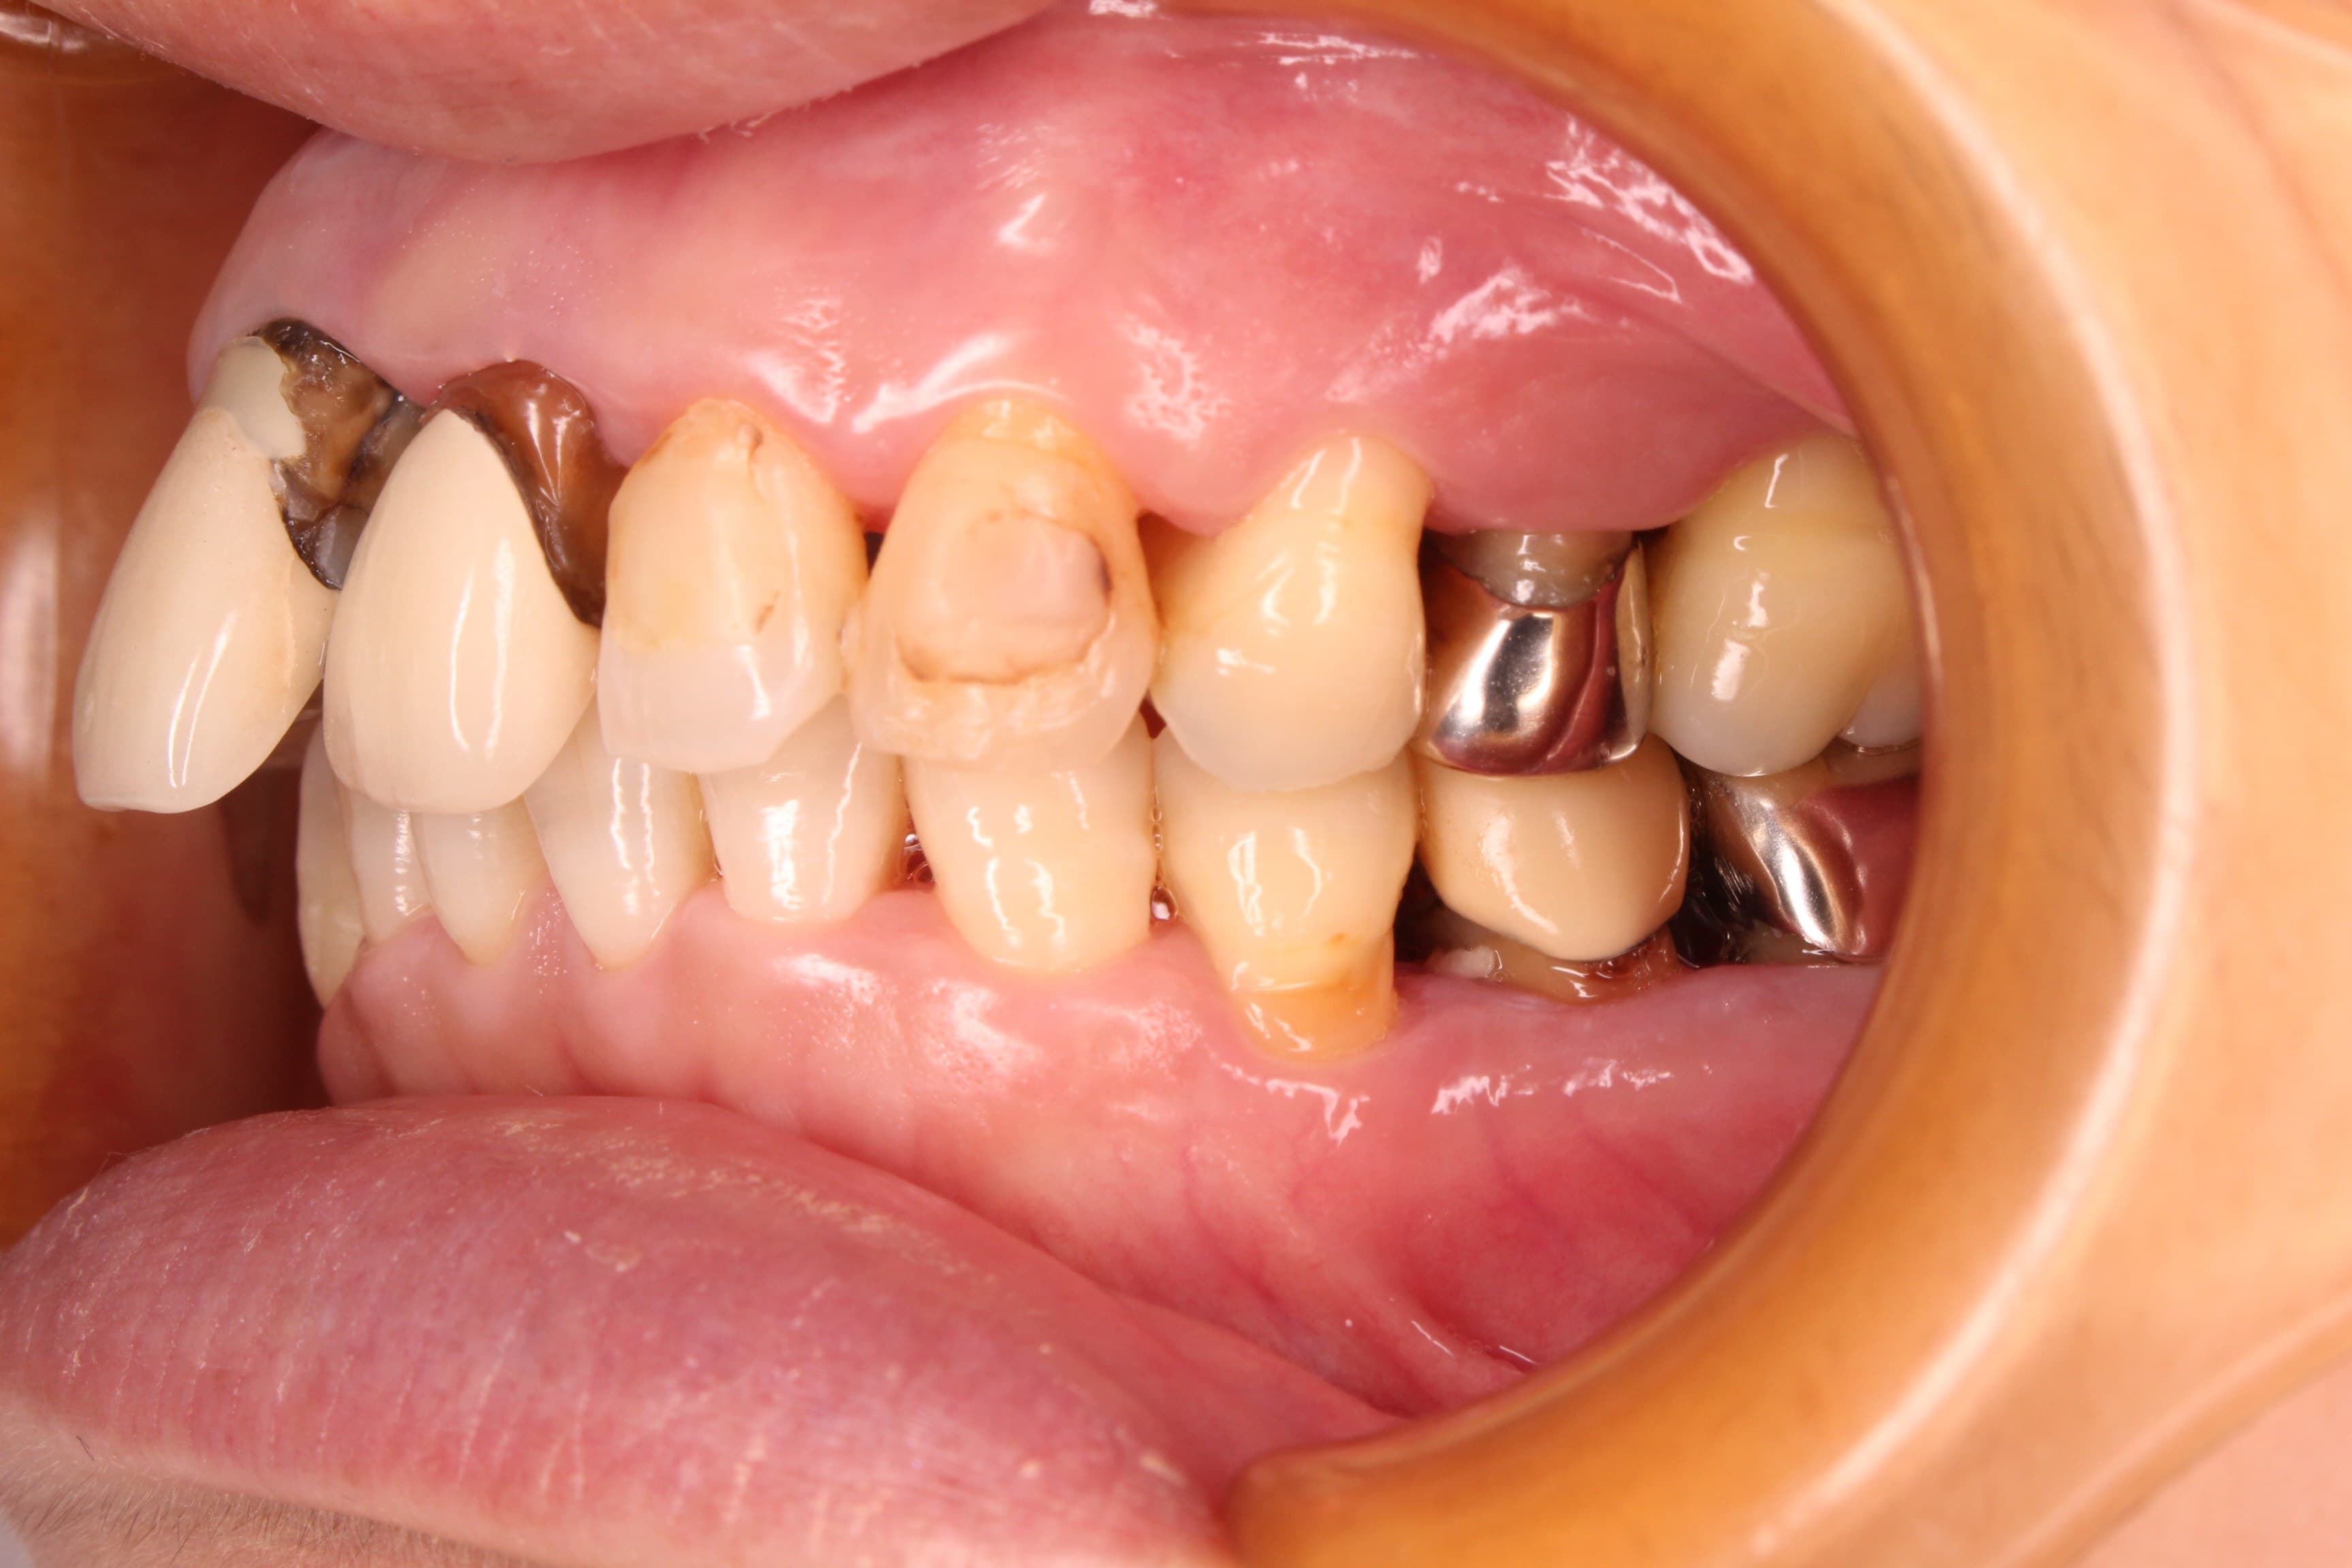

口腔内の状態は、虫歯も大きく進行し、歯周病のコントロールもされておらず、出血やプラーク、歯石等の感染物質も大量に付着していた為、虫歯の治療ができる状態ではありませんでした。

虫歯の治療はこれからですが、ブラッシングの精度もかなり高くなり、虫歯や歯周病に対する予防の知識もしっかりと習得して頂く事ができました。